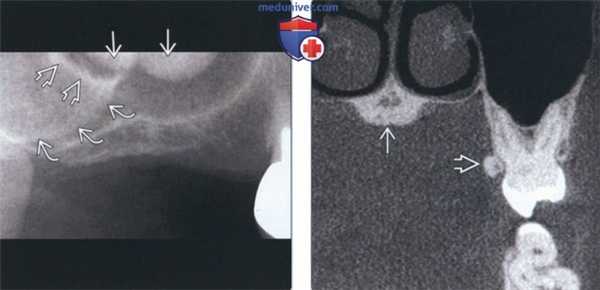

(Слева) На периапикальной рентгенограмме области средней трети корней премоляров слева определяется четко отграниченный рентгеноконтрастный участок. Такая локализация типична для нижнечелюстных валиков, хотя валики большого размера могут распространяться кзади к молярам и кпереди к резцам. Обратите внимание на отсутствие просветления на периферии. Четкие и ровные края помогают отличить валик от идиопатического остеосклероза.

(Справа) На периапикальной рентгенограмме центральных резцов нижней челюсти определяются типично выглядящие двухсторонние нижнечелюстные валики.

3. Рентгенография при нижнечелюстном валике:

• Интраоральные рентгенограммы:

о Двухсторонние хорошо отграниченные рентгеноконтрастные участки в области средней трети корней премоляров нижней челюсти

4. КТ при нижнечелюстном валике:

• КЛКТ:

о Двухсторонние экзофитные участки высокой плотности с язычной стороны в области премоляров нижней челюсти